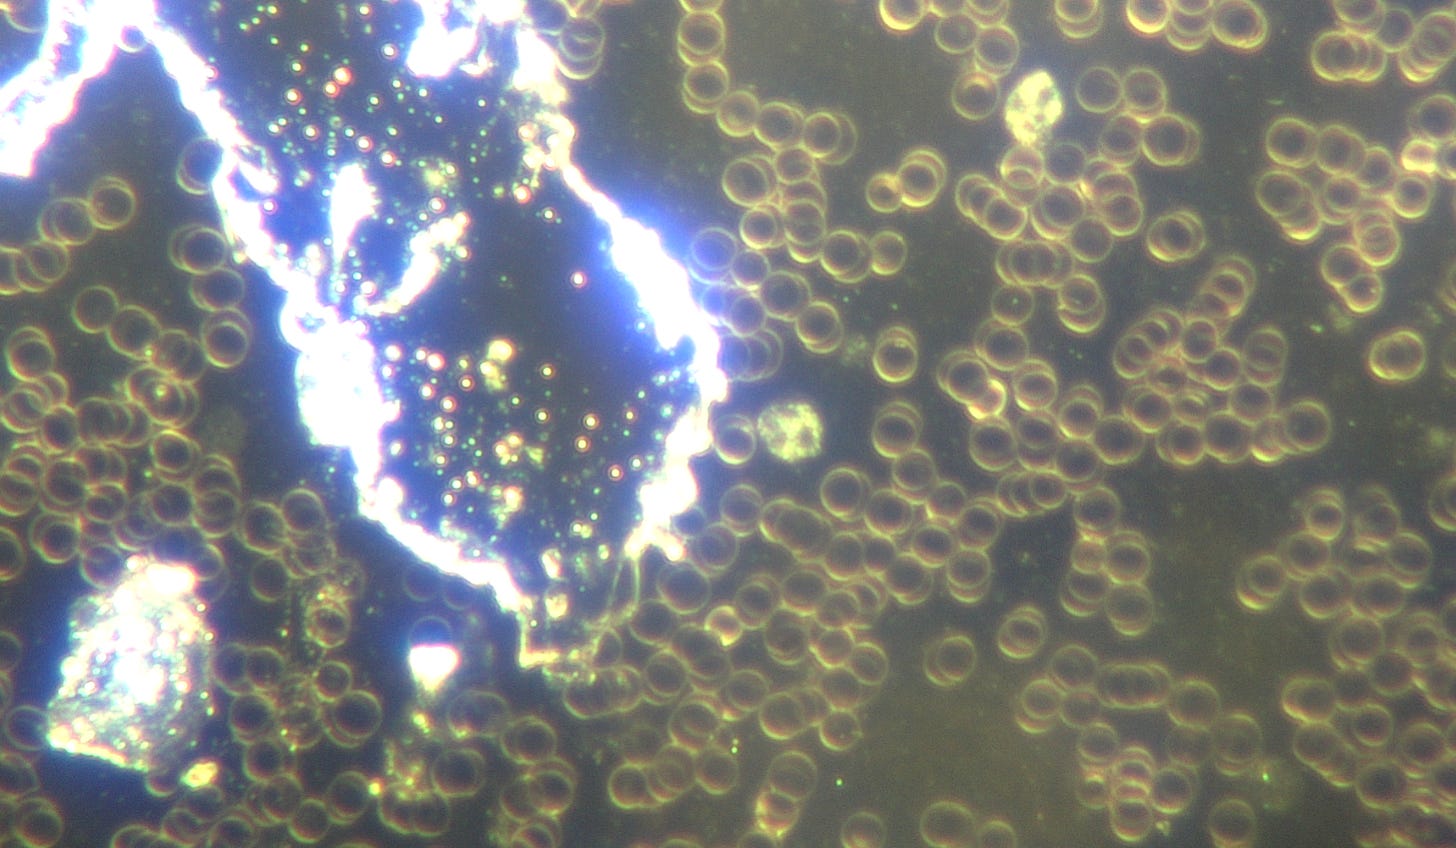

L'analyse de sang vivant que j'ai effectuée lors de son premier jour à ma clinique a révélé une nanotechnologie auto-assemblée avec un assemblage de micropuces mésogènes dans le sang :

Image : Microprocesseurs nanotechnologiques auto-assemblés et stress oxydatif du sang indiquant une récupération d’énergie. Grossissement : 100x. © Dr Ana Mihalcea